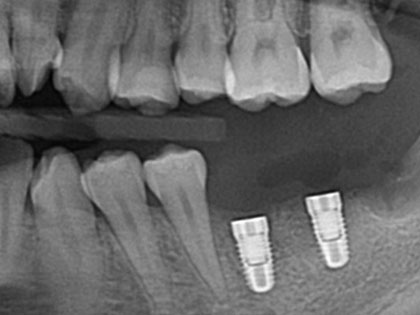

左下6が噛むと痛いため、インプラント治療を希望された患者様の症例になります

左下6が噛むと痛く、7に歯をいれたいためインプラントを希望との事で来院

治療中の写真がこちら

左下6を他院で治療後、噛むと痛い歯が破折した事で抜歯と同時に骨造成をしました。

骨が出来上がるのに4か月程待つ間に、左下親知らずが水平埋伏しており、7番目にインプラントを埋入するにあたり左下親知らずが残ったままでは汚れがたまり、結果的にインプラントもダメになる可能性があるため、親知らずを抜歯後にインプラントを埋入しました。